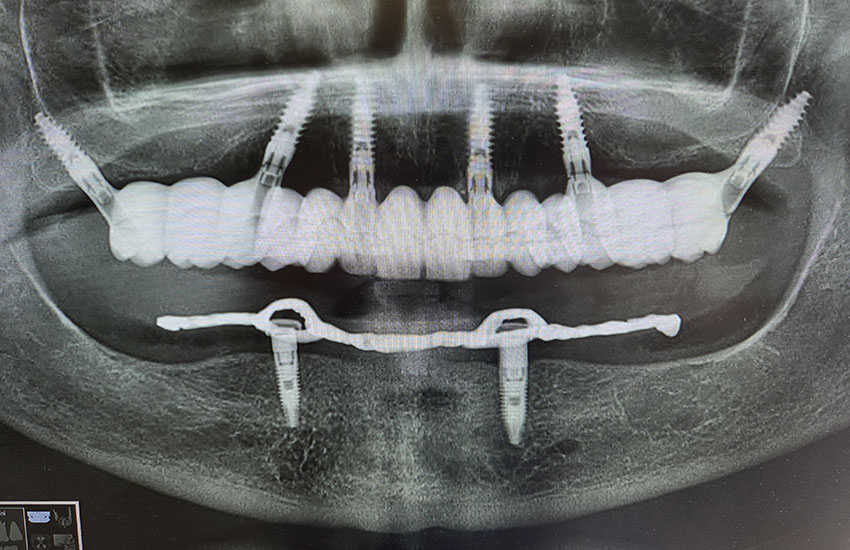

Quali sono i passaggi per arrivare ad ottenere una tale precisione? Tutto inizia dalla prima visita, dove attraverso un’ esame clinico e radiografico, si cercherà di capire se il paziente è idoneo ad una chirurgia implantare. Successivamnete inizierà la seconda fase, la più delicata, dove saranno rilevate le impronte digitali, verrà eseguita una tac volumetrica, e successivamente verranno scattate le fotografie intra ed extraorali. Nel caso del paz edentulo verrà ribasata la sua attuale protesi e scansionata, in maniera tale da poter creare una dima chirurgica perfetta per la tac

Dopo aver stabilito la nuova estetica del paziente, verranno progettati gli impianti e successivamente la dima chirurgica.

Al paziente non rimane che buttare finalmente nel cestino la sua vecchia protesi mobile o il suo vecchio ponte, in quanto questa tecnica ci consente di dimetterlo dallo studio con i suoi nuovi Denti Fissi!